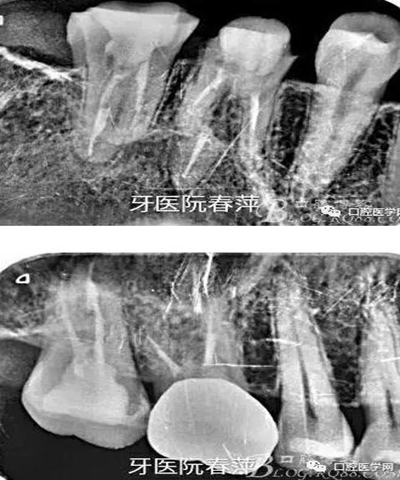

第一步,去除27的銀汞充填材料,發(fā)現(xiàn)髓腔破壞大,繼發(fā)齲明顯,牙體變色。

27的治療過程不太順利,主要是干髓近10年,根管很難疏通。腭根最先預(yù)備,比較粗大。近頰根不通暢,選中頰根找不到。

絢彩AT無飾瓷全形態(tài)氧化鋯產(chǎn)品體驗(yàn)+全冠和嵌體微創(chuàng)修復(fù)后牙

因?yàn)槿狈︼@微鏡的幫助,27的根管預(yù)備花了很長時間,最后終于找到3個根管也基本疏通到位。完善的根管治療是修復(fù)的根本,這個是什么時候都不能改變的基礎(chǔ)觀念。